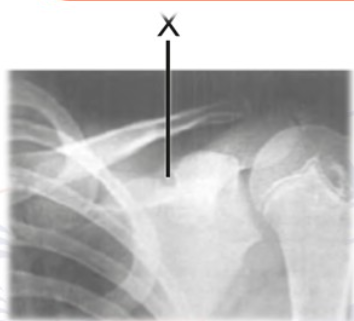

11 yaşındaki bir erkek çocuk merdivenden düşmüştür. Pratisyen hekim hastanın omuz bölgesine ait radyografisini incelemektedir.

Şekildeki “X” ile gösterilen kısım kalsifiye olmuşsa büyük olasılıkla paralizi olan kas aşağıdakilerden hangisidir?

Incisura Scapulae (X Bölgesi) İlişkileri;

Geçen Sinir: N. suprascapularis, skapulanın üst kenarındaki incisura scapulae‘den geçer.

İnnerve Ettiği Kaslar: M. supraspinatus (Omuzun ilk 15 derecelik abdüksiyonu). M. infraspinatus (Omuzun dış rotasyonu).

İncisura scapulae (skapula çentiği), skapulanın üst kenarında (margo superior) processus coracoideus‘un kökünün hemen iç tarafında bulunan çentiktir. Ligamentum transversum scapulae superius ile kapatılarak bir foramen haline gelir ve bu aralıktan n. suprascapularis geçer. Bu sinir, omuz eklemine hareket veren m. supraspinatus (ilk 15° abdüksiyon) ve m. infraspinatus (dış rotasyon) kaslarını innerve eder.

Klinik Önem: Supraskapular sinir sıkışması (entrapment neuropathy) genellikle bu çentik düzeyinde, çentiğin morfolojik varyasyonları veya ligamentin kireçlenmesi sonucu oluşabilir.